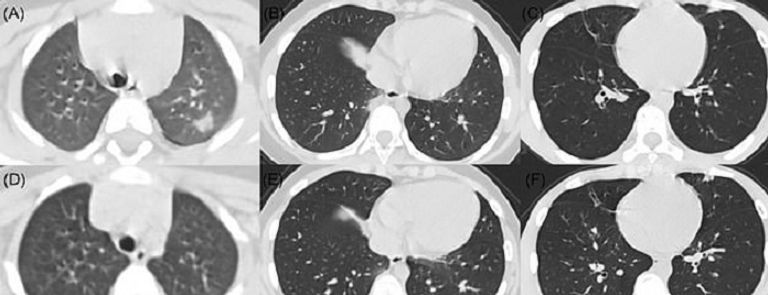

حذر أطباء نشروا أشعة مقطعية لأطفال بعد إصابتهم بفيروس كورونا المستجد من أن المرضى يمكن أن يعانوا تلفًا بالرئة.

وذكرت صحيفة "ديلي ميل" البريطانية أن فريقا من مستشفى أطفال بوسطن قيموا أشعة مقطعية لحالات إصابة من الأطفال بـ"كوفيد-19" لتحديد أبرز السمات المشتركة.

وفي دراسة على 20 طفلًا، كان نحو الثلثين لديهم ما يسمى بـ"عتامة الزجاج المطحون"، وهو مؤشر على انتشار الالتهابات.

وكان لدى نصف ما يعرف باسم "علامة الهالة"، التي تحدث عندما تحاوط الالتهابات كتلة، تعرف باسم "التصلد"، صعوبة في التنفس.

وقارن الأطباء بقيادة إخصائية الأشعة ألكسندرا فوست، الضرر جراء "كوفيد-19" مقابل أمراض أخرى تصيب الجهاز التنفسي، مثل: سارس، وميرس.

وجمعت فوست وزملاؤها 5 دراسات وأشاروا لأبرز التغييرات الملحوظة في رئة الأطفال، ونشروا نتائجهم في دورية " American Journal of Roentgenology".

وفحصت دراسة واحدة بمدينة ووهان الصينية 20 مريضًا مصابين بفيروس كورونا المستجد بمستشفى للأطفال أعمارهم ما بين يوم واحد و14 يومًا، و13 منهم كانوا ذكورا.

وكان جميع المرضى يعانون من تضرر جزء من الأنسجة أو تغيرت بشكل غير طبيعي في جدار الرئة، وكان النصف يعاني من تضررات ثنائية بالرئتين، بينما 30% كان الضرر برئة واحدة.

وكان 6 من بين 10 مرضى يعانون "عتامة الزجاج المطحون"، وهي سحابة ضبابية على الرئتين تشير لمجموعة مختلفة من المشاكل.

ويمكن أن تعني تلك السحابة أن الرئتين مملوءتان جزئيًا بمادة ملتهبة، أو أن هناك سماكة في أنسجة الرئة، أو انهيار جزئي للحويصلات الرئوية، وهي الأكياس الهوائية الموجودة بالرئتين.

وكان النصف يعانون من "التصلد"، وهو امتلاء الأكياس الهوائية في الرئتين بمواد عادة ما تكون دماء أو مياها أو صديدا.

وبعد العلاج، خضع 6 أطفال لأشعة مقطعية، وتبين أن حالات "التصلد" خفت تدريجيًا في 3 حالات.

ووجدت دراسة أصغر لـ5 مرضى صغار مصابين بفيروس كورونا المستجد حالة معتدلة من "عتامة الزجاج المطحون" بين 3 مرضى، لكنها شفيت مع الوقت.